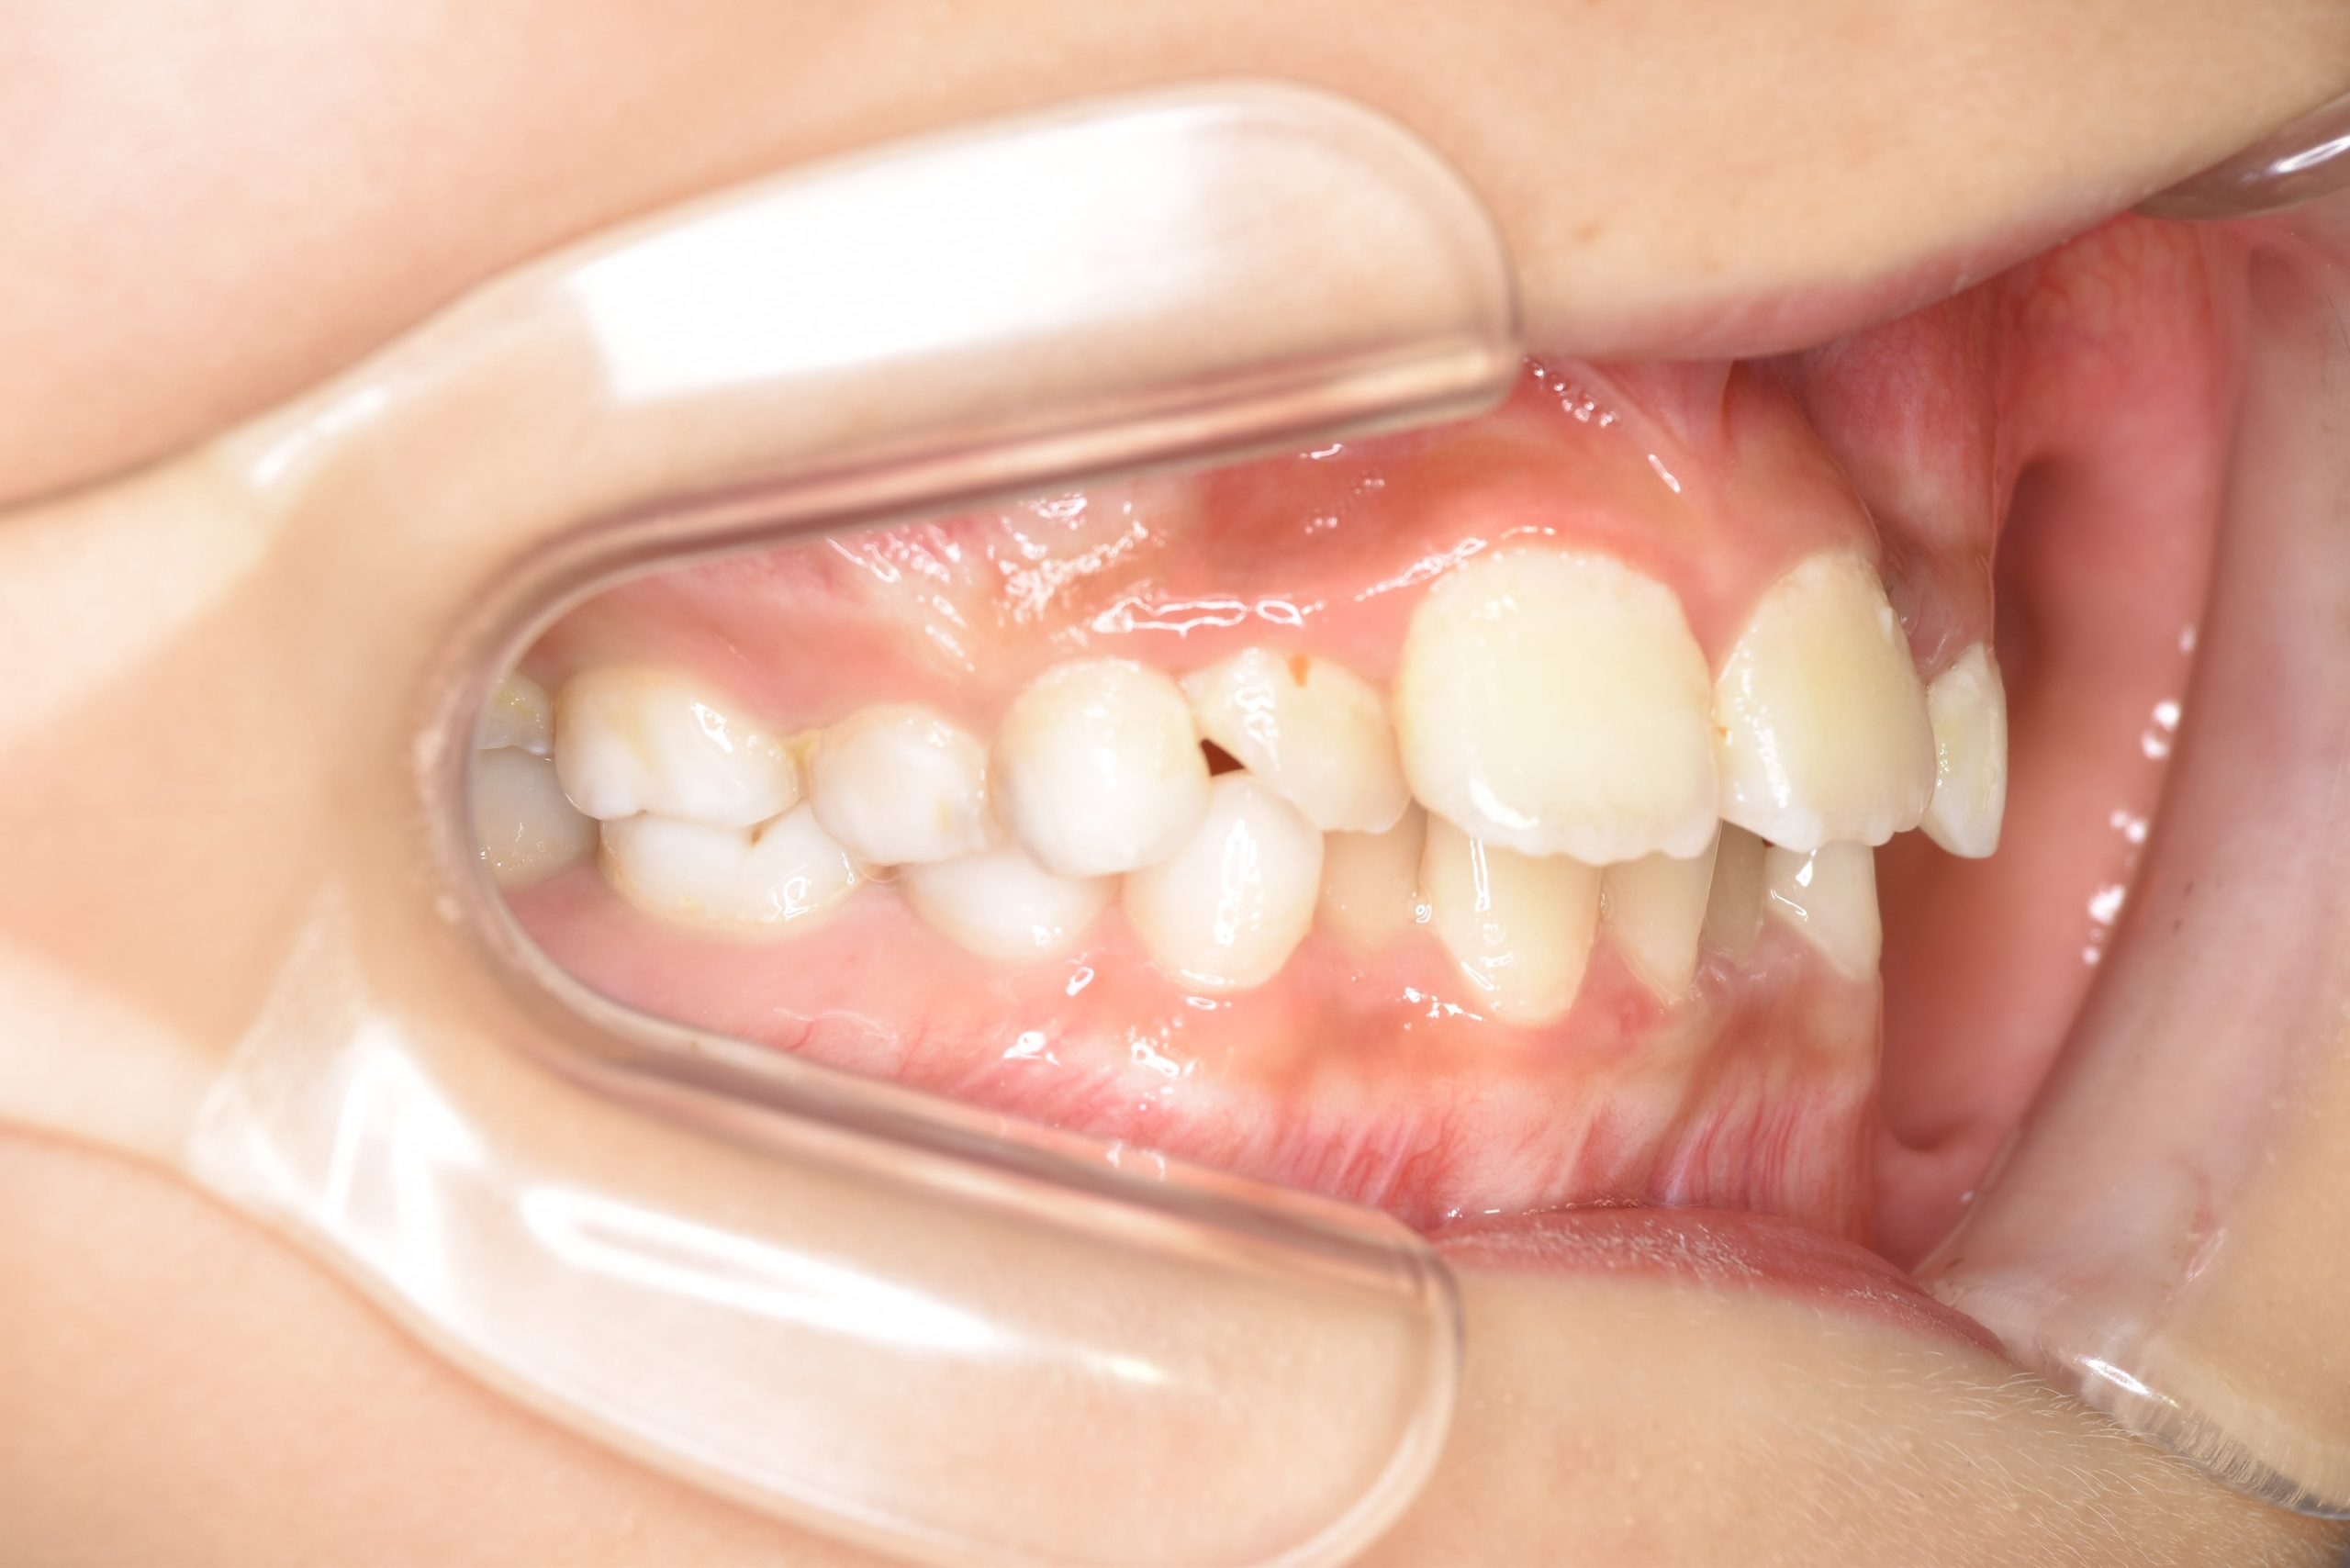

全顎ワイヤー矯正 症例_185

主訴 歯並び|横から生えている大人の歯

施術内容 小児矯正1期治療

治癒期間 4年間

費用 522,960円(税込)